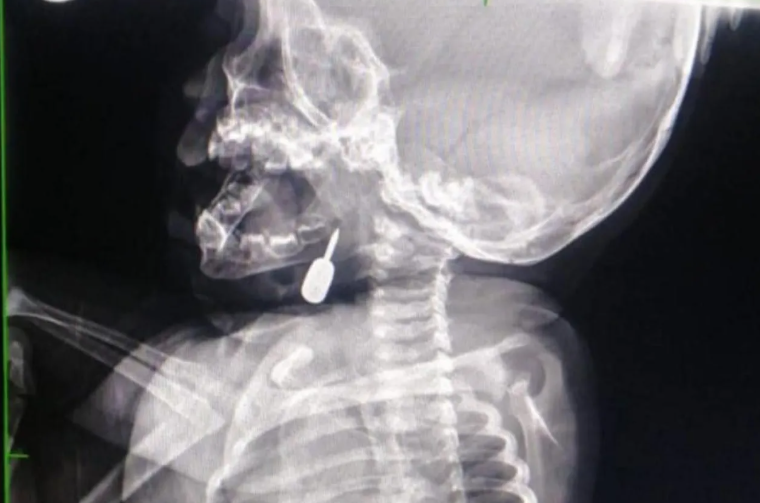

سرايا - تمكّن أخصائي الأنف والأذن والحنجرة الدكتور محمود الشبول من إجراء عملية _فتح رغامى_ تُعد الأولى من نوعها في مستشفى الملكة رانيا العبدالله، وقد تمت بنجاح.

وفي تدخل طبي عاجل، أنقذ الدكتور السبول حياة طفل يبلغ من العمر أحد عشر شهراً، بعد أن وصل إلى قسم الطوارئ وهو يعاني من حالة اختناق حادة نتيجة وجود جسم معدني عالق في منطقة الحنجرة. وقد تم استخراج الجسم بنجاح، مما أسهم في إنقاذ حياة الطفل.